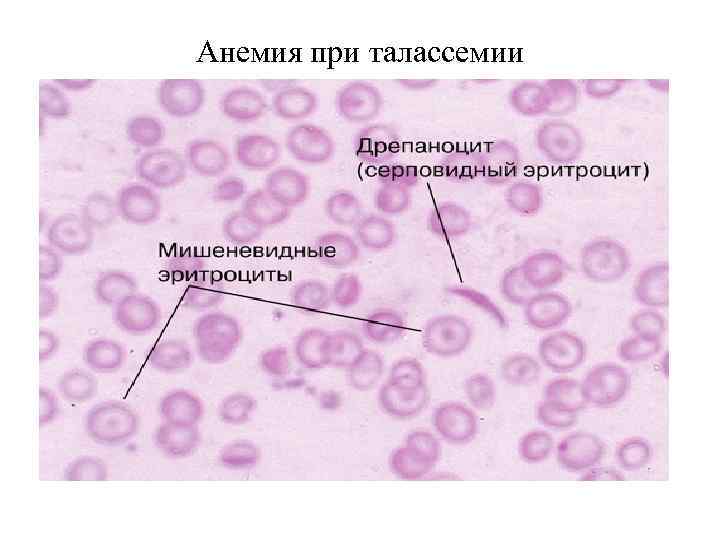

Гемограмма при гемолитической анемии • 1. Серповидноклеточная анемия, талассемия • 2. Наследственный микросфероцитоз • 3. 4. 5 Аутоиммунные

Описание гемограммы при гемолитической анемии В гемограмме имеется: 1. Микросфероцитоз 2. Гипохромия 3. Мешеневидный эритроциты 4. Серповидноклеточные эритроциты

Гемолитические анемии (внутриклеточный гемолиз): - аутоиммунные гемолитические анемии, - гемолитические анемии, обусловленные дефектами мембраны эритроцитов (наследственный сфероцитоз и др. дефекты). Наиболее вероятную основу АИГА составляет срыв иммунологической толерантности. Развивается дисбаланс в соотношении Т - хелперов и Т - супрессоров со снижением активности последних. В результате активируются Т - лимфоциты хелперы и В – лимфоциты и создаются благоприятные условия для продукции аутоантител, которые чаще относятся к классу Ig. G. Эти антитела связываются в присутствии СЗ - конвертазы комплемента с антителами мембраны эритроцитов, с последующим образованием конечного активирующего комплекса С 56789, и реализацией внутрисосудистого механизма гемолиза. Наследственные гемолитические анемии, обусловленные нарушением синтеза гемоглобина: талассемия, серповидно – клеточная анемия, гемоглобинозы. Талассемия – заболевание, связанное с нарушением скорости синтеза одного вида цепей глобина, различают: - а – талассемию, - β – талассемию, - γ - талассемию

Анемия при талассемии